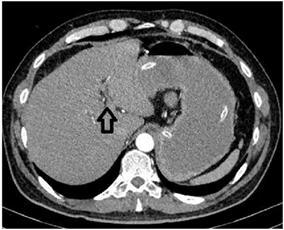

La tomografía de abdomen total simple y contrastada reportó “Vesícula biliar no visualizada, en su reemplazo se observan cambios en la densidad del hilio hepático y lecho vesicular, con colecciones de aire. A nivel de la válvula ileocecal reducción importante de calibre, no se observa cuerpo extraño ni masa, tampoco alteraciones de la grasa peri-cecal. Considerar engrosamiento o efecto estenótico parcial a nivel de válvula ileocecal que condiciona obstrucción intestinal (solo intestino delgado). Se observa distensión marcada de todas las asas delgadas desde el duodeno hasta el íleon distal” (Figura 2 y Figura 3).

Figura 2. Tomografía axial computarizada de abdomen que evidencia neumobilia en el sitio donde anatómicamente debería estar la vesícula.

La Tomografía computarizada (TAC) abdominal, permite evidenciar la ubicación del cálculo y de la obstrucción intestinal8, visualizar neumobilia, neumocolecisto, fístula bilio-entérica, niveles hidroaéreos y liquido libre en cavidad17,18, también permite identificar el tamaño del cálculo11. La tomografía se considera el patrón de oro para el diagnóstico de íleo biliar2 y si se usa contraste arroja una sensibilidad mayor al 90%19. En las imágenes del paciente, la TAC de abdomen mostró aire en el lugar de la vesícula biliar, así como distensión de asas y obstrucción a nivel de la válvula ileocecal, lo cual orientó la sospecha diagnóstica hacia íleo biliar con la consecuente intervención quirúrgica que llevó a la resolución de su obstrucción.